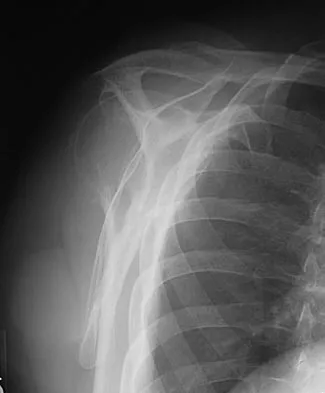

Figure 7 shows the radiograph of an 18-year-old hockey player who sustained a shoulder injury during a fall into the side boards. Examination reveals a significant prominence at the acromioclavicular joint. Management should consist of

Explanation

The radiograph shows a type V acromioclavicular separation with greater than 100% superior elevation of the clavicle. This finding implies detachment of the deltoid and trapezius from the distal clavicle. Because of severe compromise of function and potential compromise to the overlying skin, surgery is the treatment of choice for type V acromioclavicular separations. During reduction and repair, meticulous repair of the deltotrapezial fascia will also aid in securing the repair. Nuber GW, Bowen MK: Acromioclavicular joint injuries and distal clavicle fractures. J Am Acad Orthop Surg 1997;5:11-18.